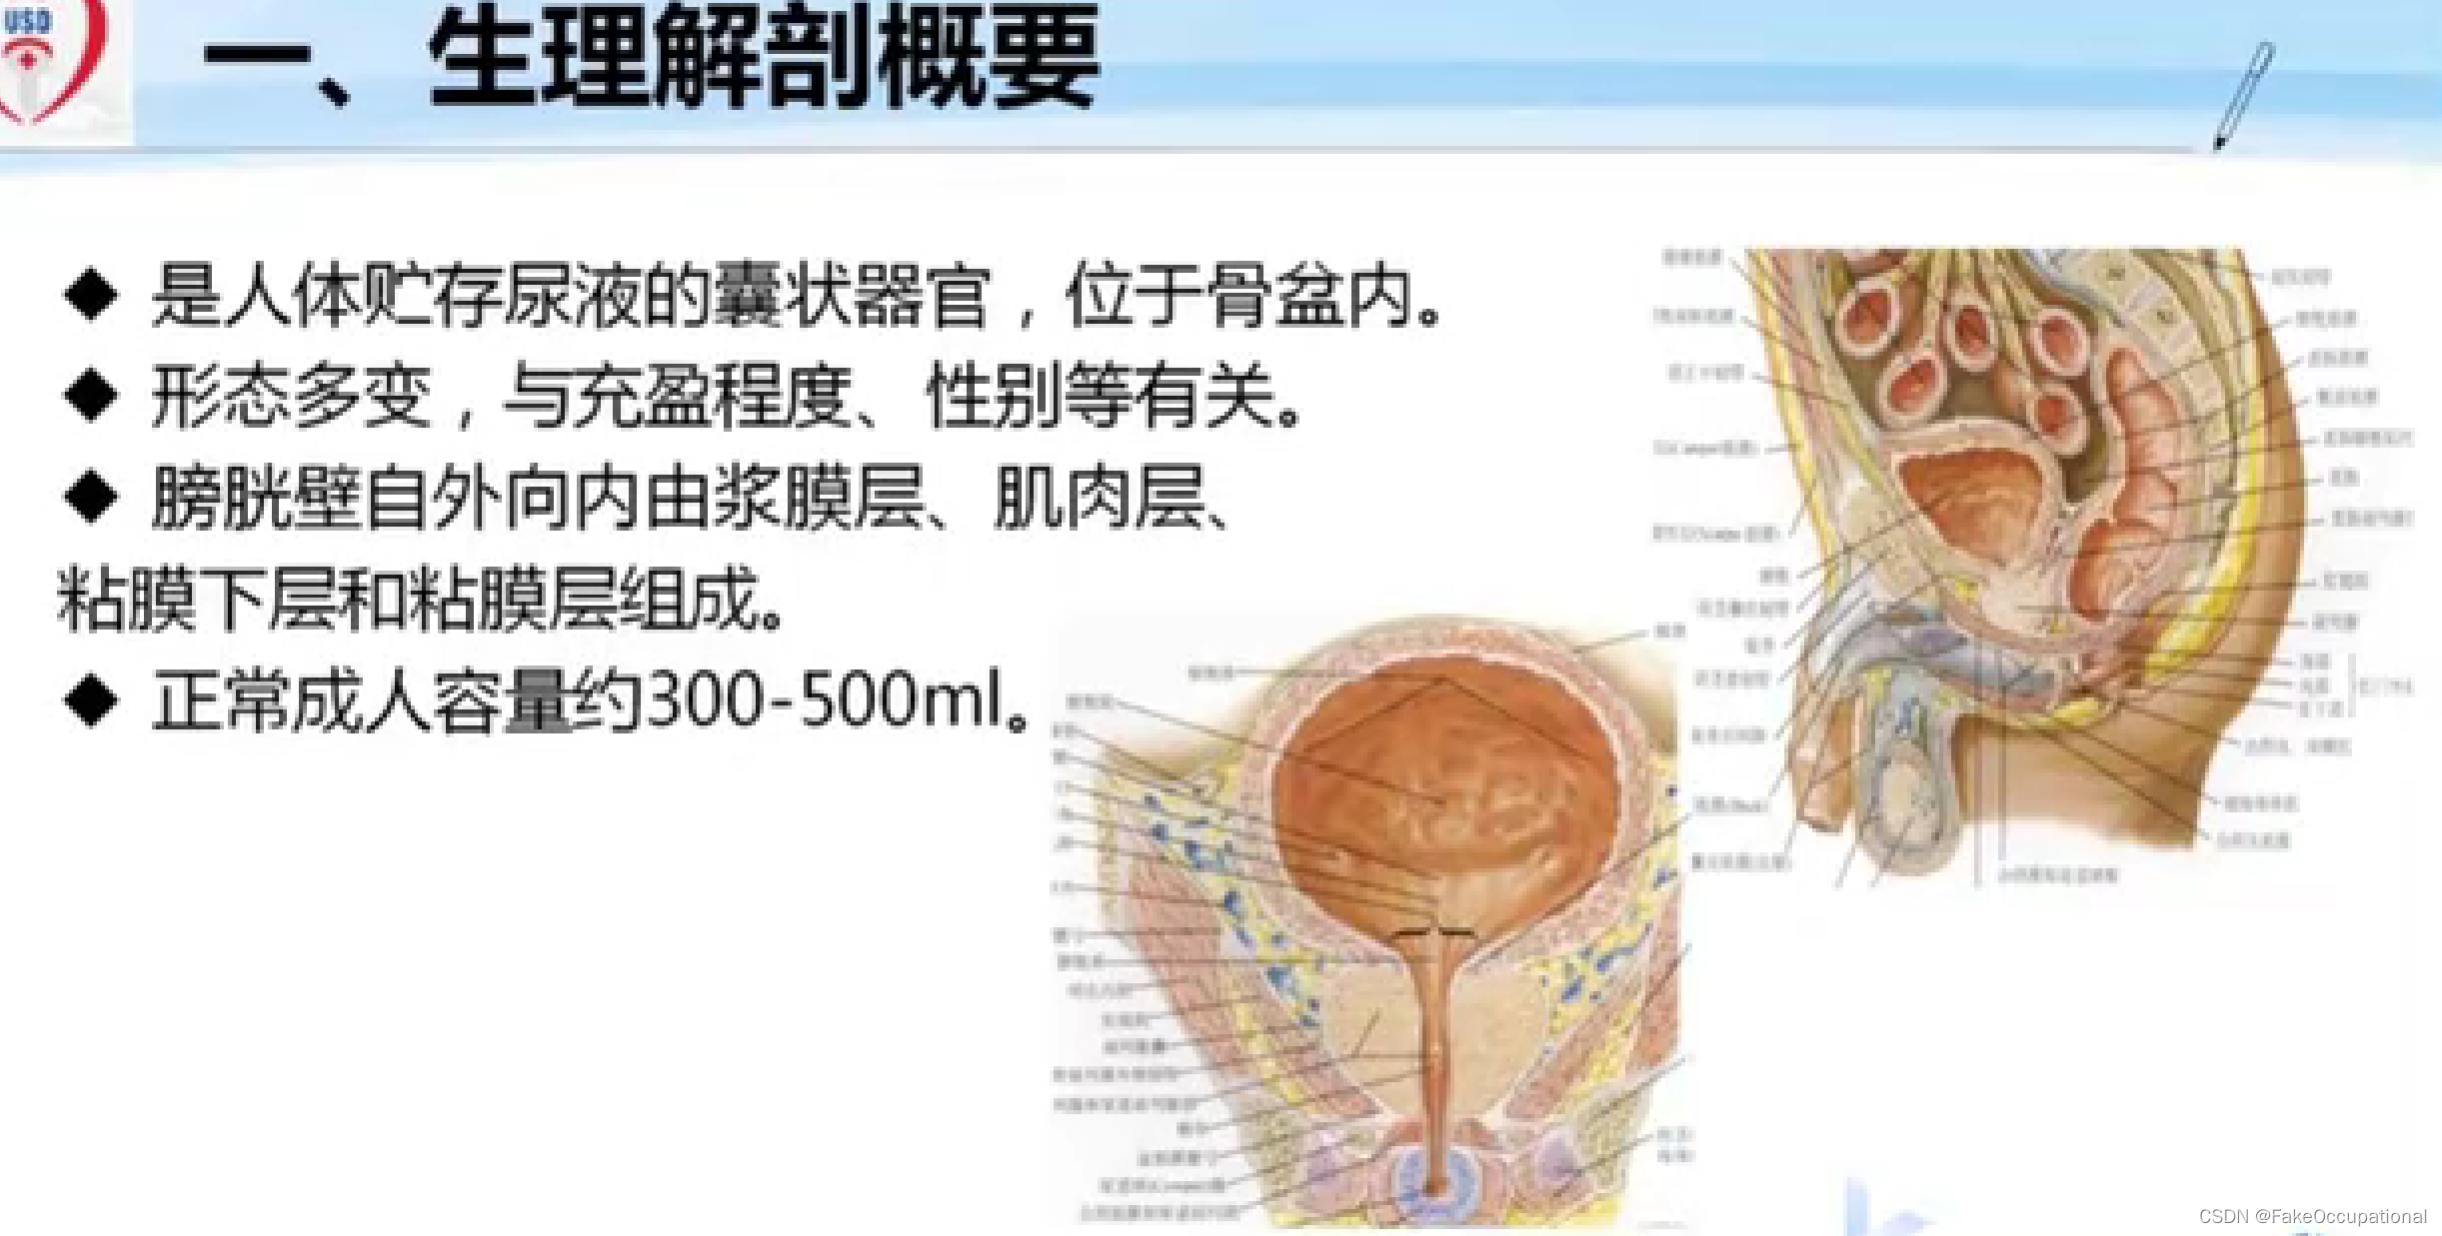

膀胱超声

1、检查前准备

检查前40分钟饮水500ml充盈膀胱,直至有尿意

2、探测方法

经腹壁探查:仰卧位,探头放置耻骨上。经直肠检查:排便或灌肠一次少量尿液即可,取膝胸位、截石位或左侧卧位,探头插入肛门。